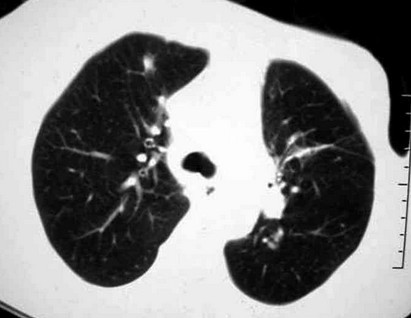

2、肺部表现:既然胸部会受到强直的很多影响,那么,肺部当然避免不了要深受其害了,一般的很多病人都会出现各种情况的咳嗽或者气短的情况,当然也会有反反复复的肺炎的出现,这就是比较常见的患者会受到肺部损害的典型的症状了!很多患者想了解强直的治疗费用,您可以点击强直性脊柱炎治疗费用需结合实际的病情具体看一下。